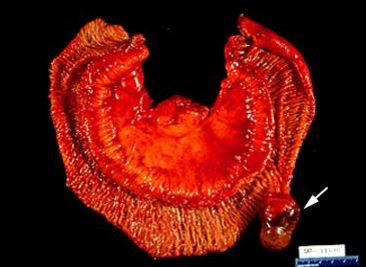

On gastrointestinal endoscopy, the PJP have no major distinguishing features, and may be sessile, pedunculated, or lobulated. The number of polyps ranges from 1 to more than 20 per segment of bowel, although some patients have solitary lesions. The size of the polyps ranges from 0.1 to more than 5 cm in diameter (picture 2). On histology, PJ P are hamartomas that characteristically contain a proliferation of smooth muscle extending into the lamina propria in an arborization-like fashion; the overlying epithelium is normal (picture 3). Epithelial misplacement involving all the layers of the bowel has been reported in  approximately 10 percent of small intestinal polyps in PJS. Epithelial misplacement, possibly due to mechanical forces, may extend into the serosa and be misdiagnosed as a well-differentiated adenocarcinoma.

Picture 2: Gross picture of an intestinal polyp (arrow) removed from a patient with the PJS.